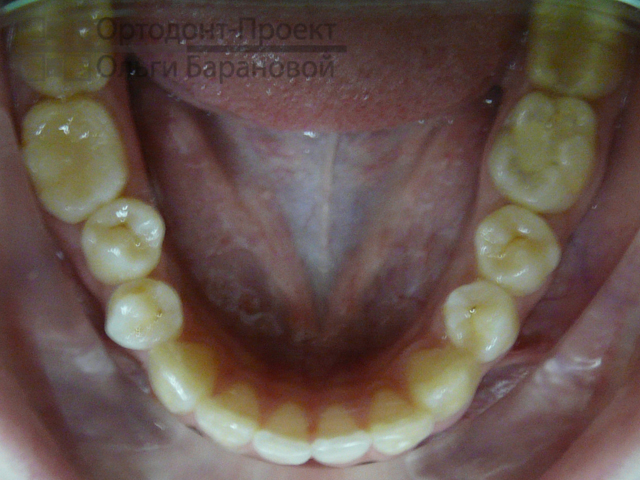

Диагноз ортодонта: ротация 35, 34, 44, 45 зубов. Сужение нижнего зубного ряда, сужение и укорочение верхнего зубного ряда. Глубокая резцовая окклюзия, смещение нижнего косметического центра вправо, дистальная окклюзия.

Исходная ситуация: